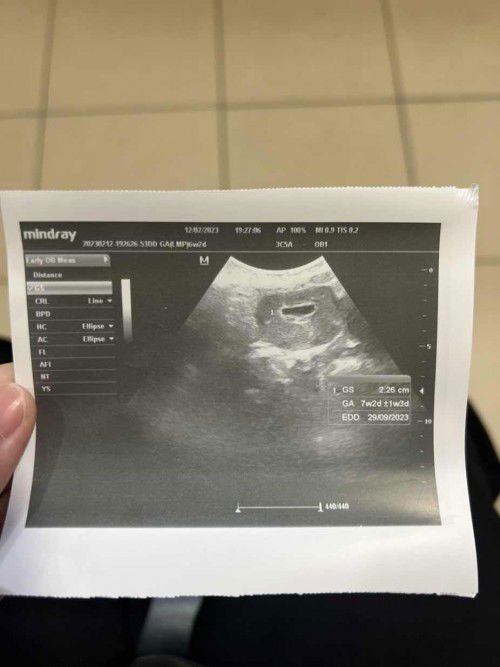

Sepatutnya kandungan saya 6w2d (ikut tarikh last period) , tapi bila scan 7w2d. Normal ke kalau tak nampak heartbeat ? Doc suruh repeat scan lagi 2 minggu. Kenapa ye kantung leper macam tu? Doc cakap kalau ada bleeding ke cepat2 dtg klinik. Ada kemungkinan kandungan tak jadi ke?